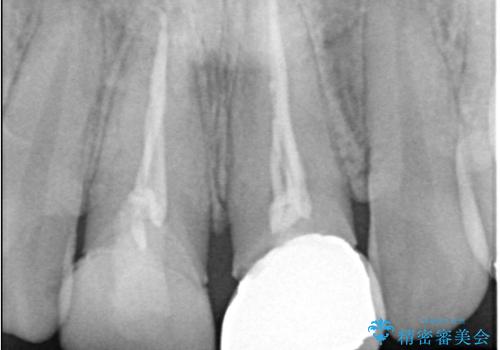

- 以前他院で治療した前歯の被せものの見た目の不満を主訴にご来院されました。レントゲンと診査の結果、被せものの不適合だけでなく、その土台となる歯の根管充填(根の治療の詰め物)が不十分であることが判明。再感染のリスクを避けるため、まず精密根管治療を行い、その後に最も審美性に優れたオールセラミッククラウンで修復する治療計画を立案しました。これにより、見た目の改善と歯の寿命の長期化を目指しました。

治療は、再感染の原因となっていた粗な根管充填材を丁寧に取り除く精密根管治療から開始しました。治療中はラバーダムと歯科用顕微鏡を使用し、根管内を徹底的に清掃・消毒。根の先まで緊密に薬を詰めることで、再発リスクを最小限に抑えました。根管治療の完了後、歯ぐきの状態を整え、周囲の歯と調和するオールセラミッククラウンを作製。金属を一切使わないため、透明感のある自然な仕上がりとなり、長年の見た目のコンプレックスも解消。歯の内部から表面までを根本的に改善することができました。